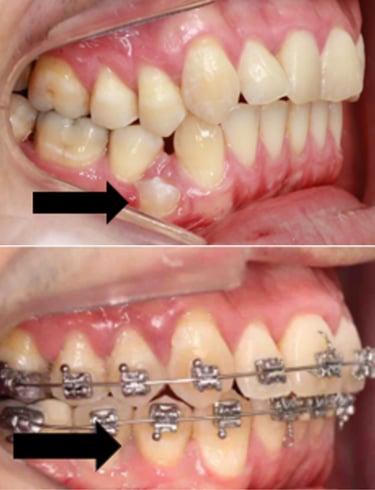

EVOLUÇÃO